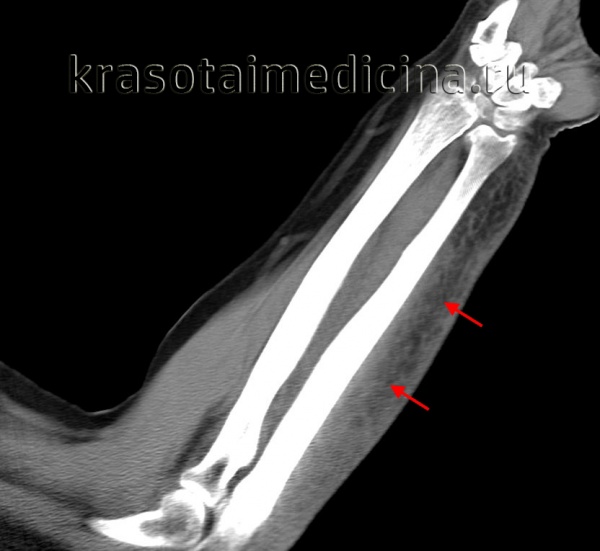

КТ предплечья может выявить геморрагическое пропитывание и отек мягких тканей со стороны лучевой кости (ушиб, подкожная гематома).